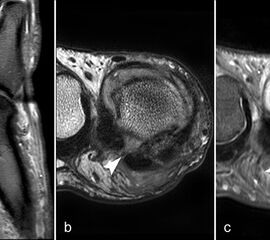

Sesambeine

Die zystischen Veränderungen und die angrenzende Skleros

Abbildung 14

Pathologische Veränderungen der Sesambeine können erhebliche Beschwerden verursachen. Die Unterscheidung einer Fraktur von einem bipartiten Sesambein ist am einfachsten röntgenologisch möglich, da bei einem bipartiten Sesambein die zwei Kerne abgerundet sind und sich nicht wie zwei zusammen passende Puzzlestücke zu einem „ganzen“ Sesambein ergänzen. Findet sich in der MRT ein völlig normales Fettsignal in beiden Anteilen, kann man ebenfalls von einem bipartiten Sesambein ausgehen. Sind ein oder beide Teile in T1 signalgemindert, kann es sich um eine Stressreaktion (Abb. 14) oder auch Nekrose bei vorbestehendem bipartitem Sesambein aber auch um eine Fraktur mit Pseudarthrosenbildung handeln. Die ätiologisch oft unklare entzündliche Aktivierung eines Sesambeins wird als „Sesamoiditis“ bezeichnet 67.